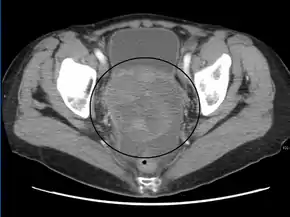

CT scanning is preferred to assess the extent of the tumor in the abdominopelvic cavity, though magnetic resonance imaging can also be used.[28] CT scanning can also be useful for finding omental caking or differentiating fluid from solid tumor in the abdomen, especially in low malignant potential tumors. However, it may not detect smaller tumors. Sometimes, a chest x-ray is used to detect metastases in the chest or pleural effusion. Another test for metastatic disease, though it is infrequently used, is a barium enema, which can show if the rectosigmoid colon is involved in the disease. Positron emission tomography, bone scans, and paracentesis are of limited use; in fact, paracentesis can cause metastases to form at the needle insertion site and may not provide useful results.[29] However, paracentesis can be used in cases where there is no pelvic mass and ascites is still present.[29] A physician suspecting ovarian cancer may also perform mammography or an endometrial biopsy (in the case of abnormal bleeding) to assess the possibility of breast malignancies and endometrial malignancy, respectively. Vaginal ultrasonography is often the first-line imaging study performed when an adnexal mass is found. Several characteristics of an adnexal mass indicate ovarian malignancy; they usually are solid, irregular, multilocular, and/or large; and they typically have papillary features, central vessels, and/or irregular internal septations.[31] However, SCST has no definitive characteristics on radiographic study.[33]

In advanced cancers, where complete removal is not an option, as much tumor as possible is removed in a procedure called debulking surgery. This surgery is not always successful, and is less likely to be successful in women with extensive metastases in the peritoneum, stage- IV disease, cancer in the transverse fissure of the liver, mesentery, or diaphragm, and large areas of ascites. Debulking surgery has usually only been done once[28] but a recent study has shown a longer overall survival in recurrent ovarian cancer when surgery combined with chemotherapy was performed compared to treatment with chemotherapy alone.[94] Computed tomography (abdominal CT) is often used to assess if primary debulking surgery is possible, but low certainty evidence also suggests fluorodeoxyglucose‐18 (FDG) PET/CT and MRI may be useful as an addition for assessing macroscopic incomplete debulking.[95] More complete debulking is associated with better outcomes: women with no macroscopic evidence of disease after debulking have a median survival of 39 months, as opposed to 17 months with less complete surgery.[26] By removing metastases, many cells that are resistant to chemotherapy are removed, and any clumps of cells that have died are also removed. This allows chemotherapy to better reach the remaining cancer cells, which are more likely to be fast-growing and therefore chemosensitive.[29]